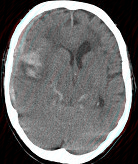

- 单项选择题女,79岁, 突发神志不清,请结合影像图像判断其最可能的诊断 ( )

A、脑转移瘤出血

B、脑脓肿

C、脑梗死

D、右大脑中动脉破裂出血

E、脑膜炎